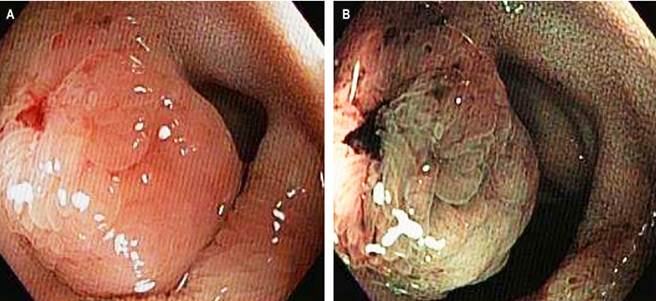

This is a 56-year-old female patient with a history of difficult-to-manage hypertension (HTN) since 2022. In the search for the origin of the HTN, she underwent various studies: a normal total abdominal ultrasound, an abdominal and pelvic MRI with contrast, which revealed pancreatic cysts, and an endoscopic ultrasound with biopsy, which provided a histological diagnosis of mucinous pancreatic cysts. She was referred to gastroenterology due to diffuse colicky abdominal pain associated with bloating and two soft stools per day, which had been present for two years. A colonoscopy with ileal intubation was performed, revealing a 15 mm sessile polypoid elevated lesion in the distal ileum, 5 cm from the ileocecal valve (Figure 1). The pathology report from the lesion biopsies showed the presence of a well-differentiated, low-grade NET (Grade I), with a mitotic count of 0-1 per mm2, CKAE1/AE3: positive, focal, extranodal extension, and strong positivity for synaptophysin, chromogranin, and enolase (Figure 2).